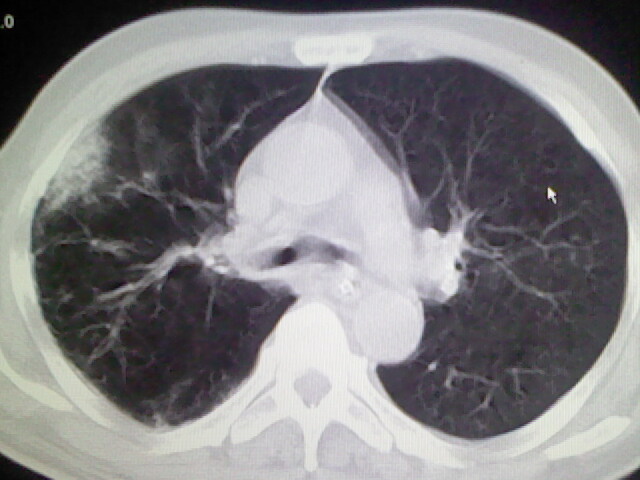

男,70岁,脑出血,长期卧床,左侧背部可触及肿块

右肺病灶考虑炎症性。

右肺病灶考虑炎症性

考虑右肺及左肺下叶炎症。

右肺及左肺下叶炎症。

考虑右肺及左肺下叶慢性炎症。

右侧肺部见片状密度增高影,边缘模糊。考虑炎症。另食管壁增厚。

右肺上叶前段病呈楔形,其尖端指向肺门,考虑肺动脉栓塞可能性大.